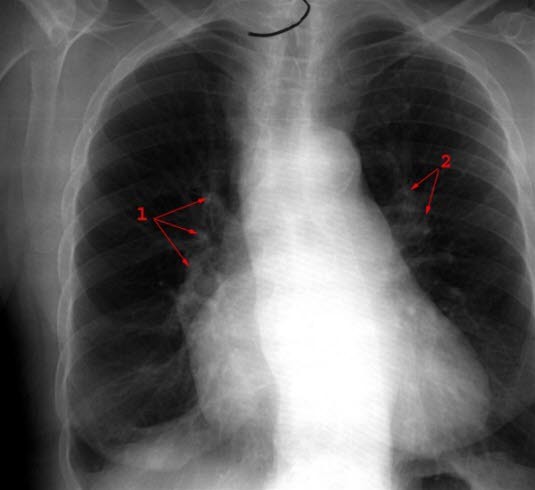

Når diagnosen høyt blodtrykk i lungekretsløpet mistenkes, kreves omfattende utredning i sykehus. Sikker diagnose stilles ved direkte måling av trykket i lungearterien under såkalt hjertekateterisering. Man kan også få gode målinger med EKKO-undersøkelse av hjertet. I tillegg kan det være nødvendig med en rekke andre undersøkelser:EKG og lungefunksjonsmålinger, røntgen av hjerte og lunger, lungescintigrafi, CT og MR, samt målinger av blodgasser. Hvilke undersøkelser som er nødvendig avgjøres i hvert enkelt tilfelle.